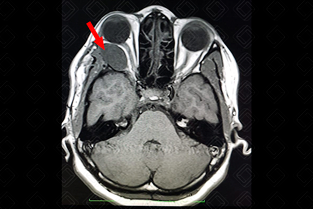

Texto alternativo para a imagem Figura 2. Créditos: Dra. Elazir Mota - Rio de Janeiro/RJ

Descrição da figura 2: Mesmo paciente, imagem axial ponderada em T2, evidenciando lesão com hipersinal, discretamente heterogêneo (seta vermelha).

• Ressonância magnética do crânio: S ão heterogeneamente hiperintensos em T2. Nas imagens ponderadas em T1, são iso ou hipointensos, com ávido realce pelo meio de contraste. A clássica imagem do schwannoma é no ângulo pontocerebelar, pelo acometimento mais comum do VIII par (figuras 1, 2 e 3).